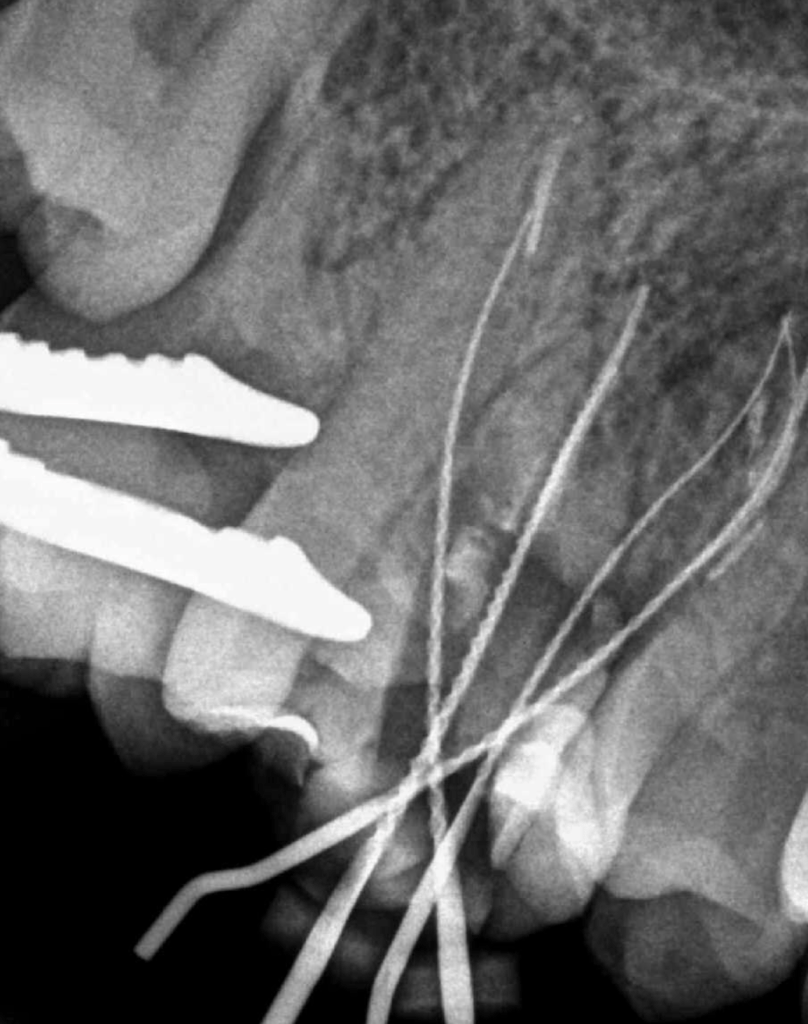

Reco preendo + 4 conductos molar superior